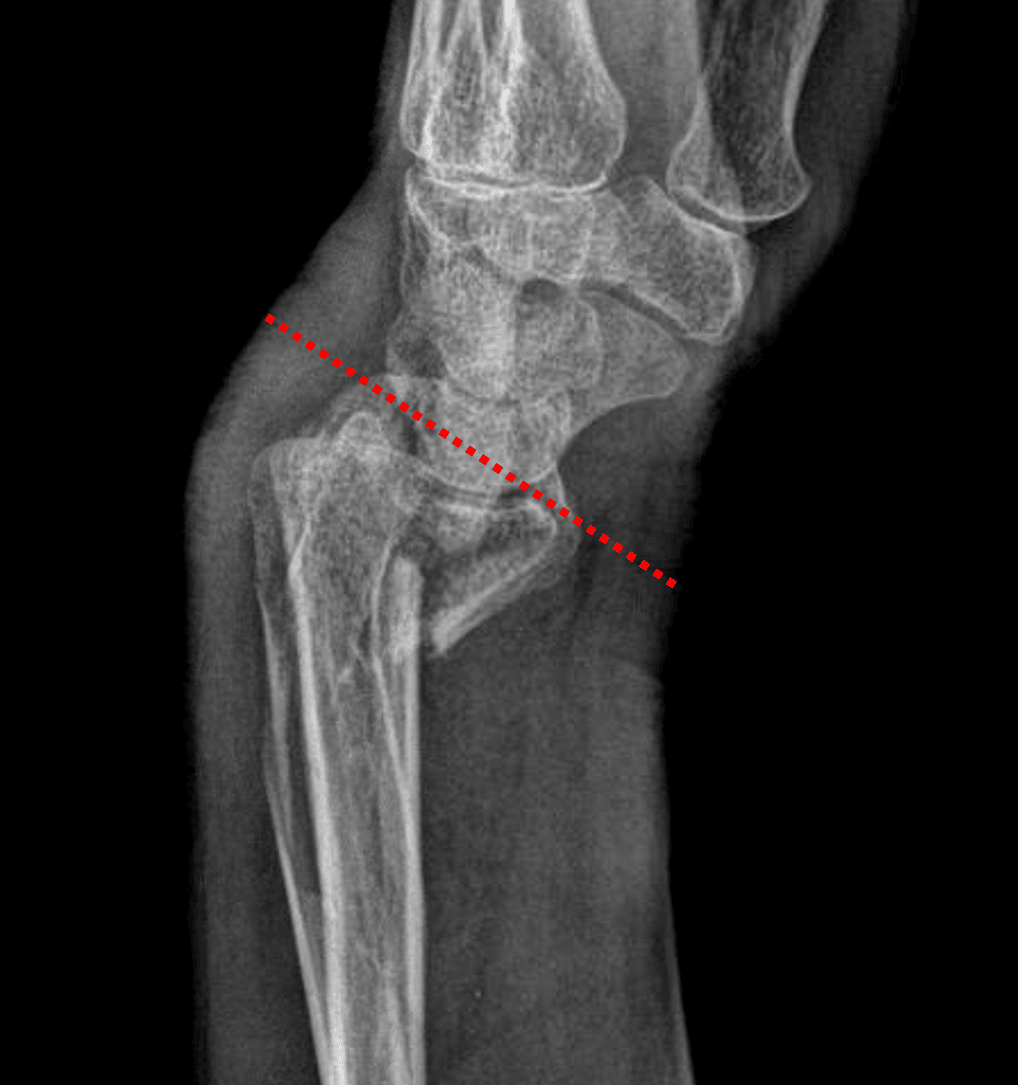

Smith fracture with volar displacement and volar angulation of the distal radial articular surface (red dotted line).

• Acute comminuted, impacted, transverse distal radial metaphyseal fracture with mild volar displacement, volar angulation of the distal radial articular surface, and extension into the radiocarpal joint

Smith fracture (Frykman IV)